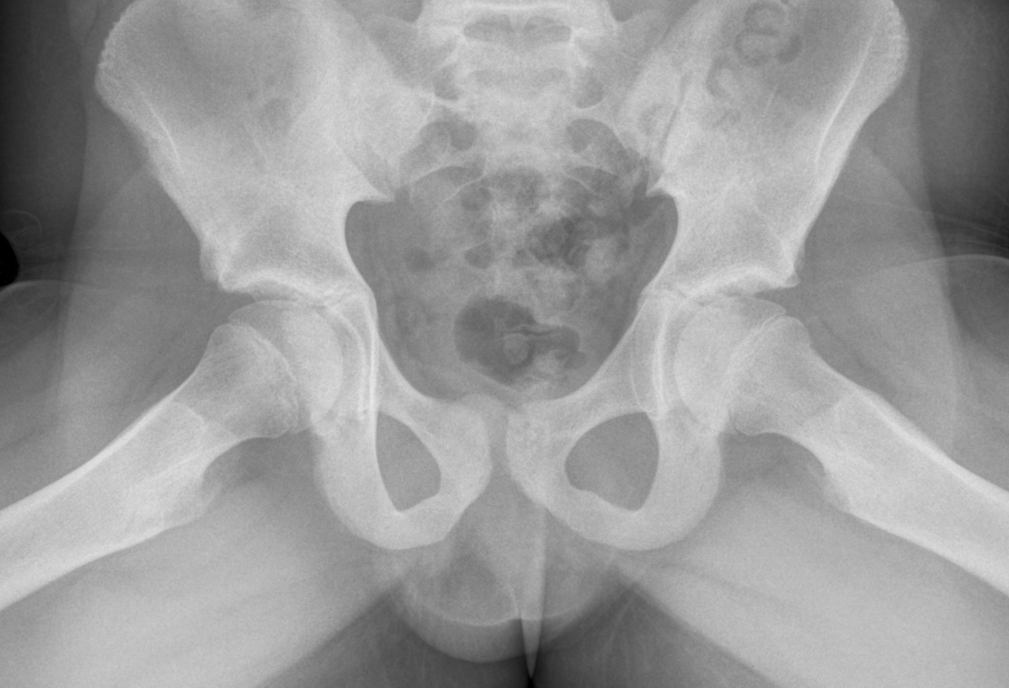

3. Frog lateral view